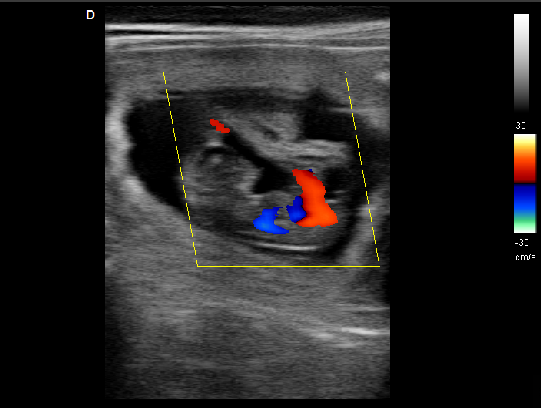

P5-VET獸用彩超機脊椎檢查圖

脊椎檢查:

脊柱裂的預防和確診,一般在動物懷孕以后定期給動物做超聲檢查,通過超聲、超聲檢查可以早期發現動物胎兒是否合并了脊柱裂或是神經管閉合不全。